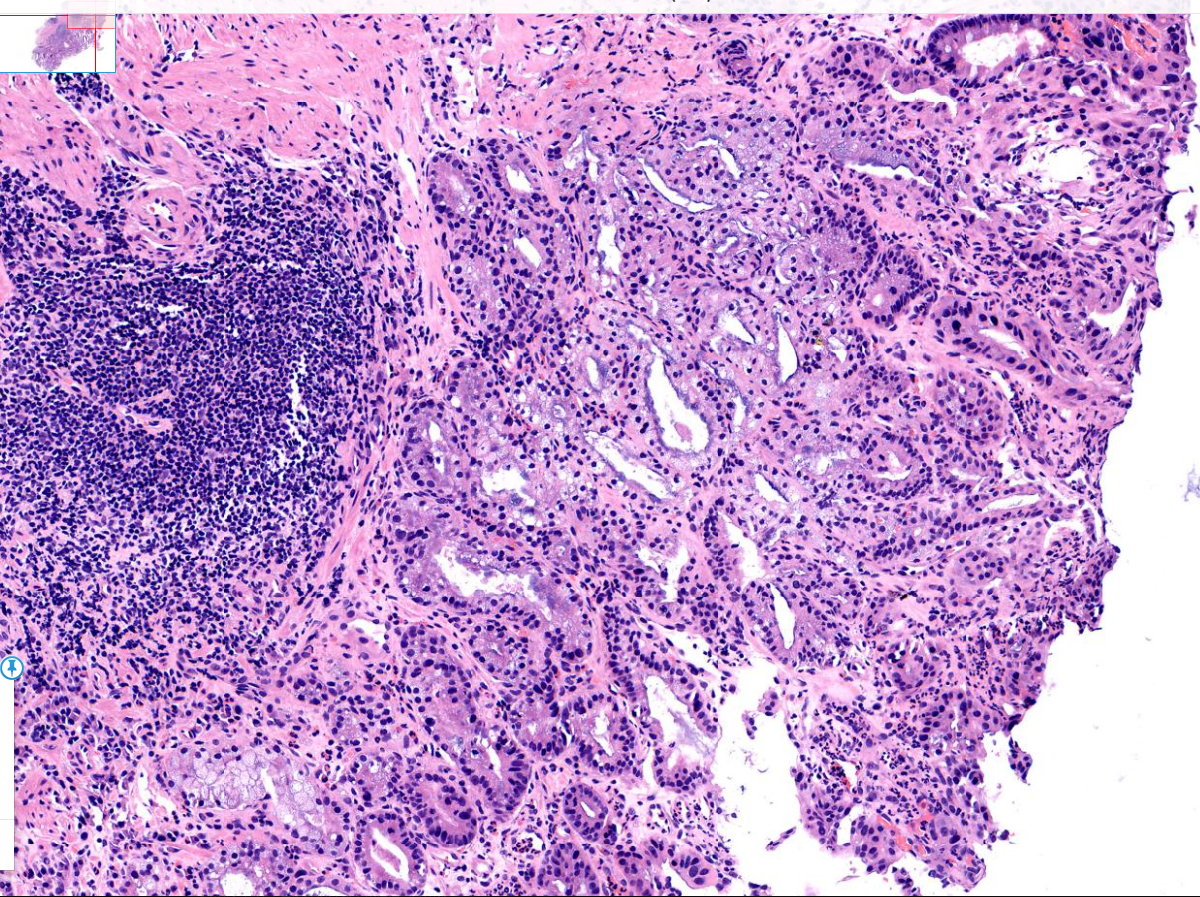

胃体活检

性别

男

年龄

77岁

临床诊断

一般病史

体检

标本名称

胃体

大体所见

胃体粘膜浅表凹陷

考虑为萎缩肠化伴糜烂部分腺体考虑为反应性修复性增生伴淋巴滤泡形成

有高级别上皮内瘤变

慢性萎缩性胃炎伴肠化,图4有高级别

早癌